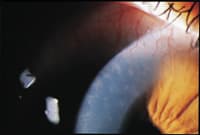

Figure 2a and 2b. Patient's left eye at the time of his initial

presentation. |

The patient presented with a three-day history of red eyes, mild discomfort and a decreased wearing time. Slit lamp examination revealed 2+ conjunctivial injection, diffuse corneal edema, 360 degrees of peripheral neovascularization and multiple peripheral and mid-peripheral infiltrates (Figures 1a, 1b, 2a and 2b).